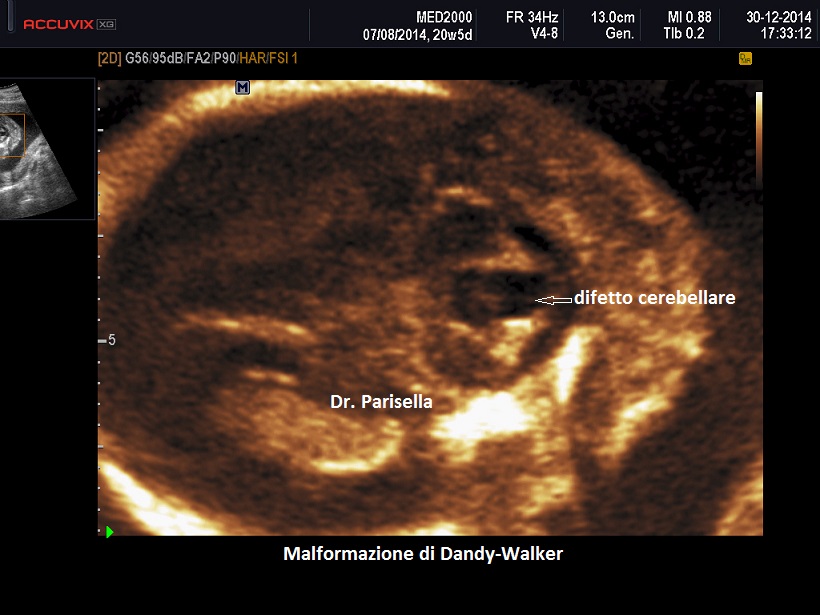

Sindrome o Malformazione di Dandy-Walker

La malformazione di Dandy-Walker ha una incidenza di circa 1/30.000 nati ed è caratterizzata da agenesia totale o parziale del verme cerebellare e dilatazione cistica del 4° ventricolo; se il verme è ipoplasico esso appare dislocato anteriormente e superiormente.

La diagnosi ecografica si basa su:

• dilatazione cistica del IV ventricolo che si estende occupando gran parte della fossa cranica posteriore; la cisterna magna è compressa tra il 4° ventricolo dilatato e la dura madre

• ipogenesia o agenesia del verme cerebellare

• ampia separazione degli emisferi cerebellari: caratteristica è la schisi a "V" del verme cerebellare nel piano assiale

• sul piano mediano il 4° ventricolo dilatato si estende superiormente dislocando il verme cerebellare, che è frequentemente ipoplasico